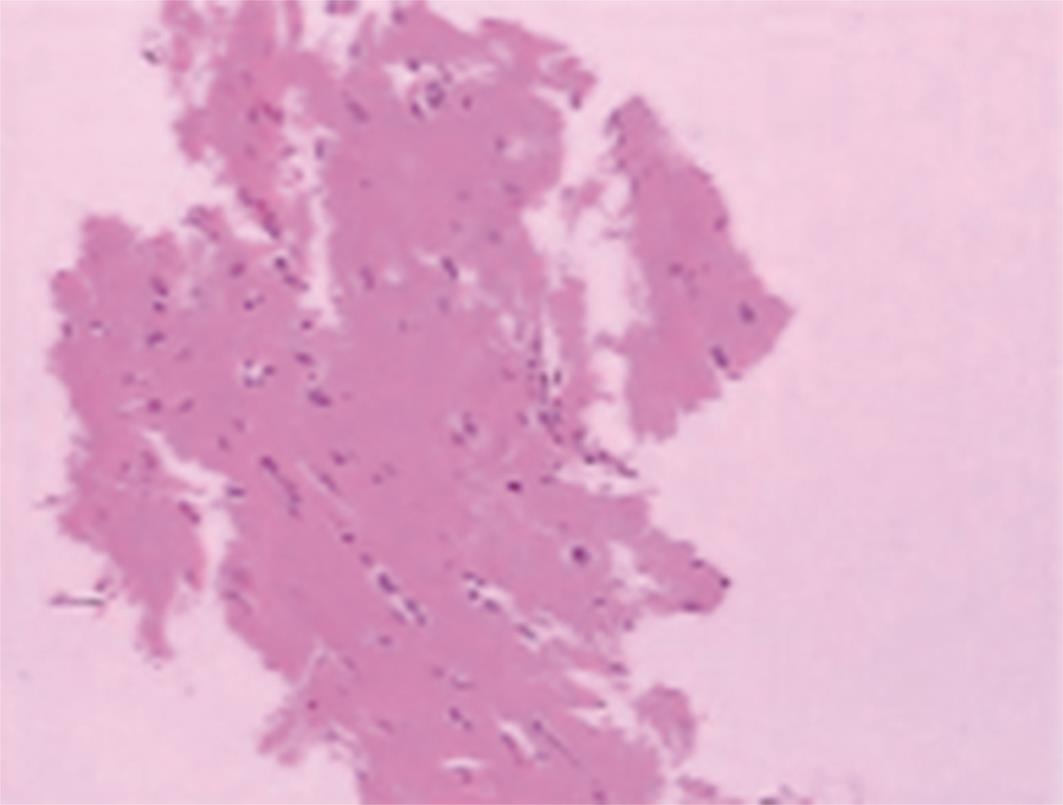

• 肿瘤样脱髓鞘病变报道3例

2023, 48(5):614-617. DOI: 10.13406/j.cnki.cyxb.003183

摘要 (95) HTML (24) PDF 1.29 M (241) 评论 (0) 收藏

摘要: